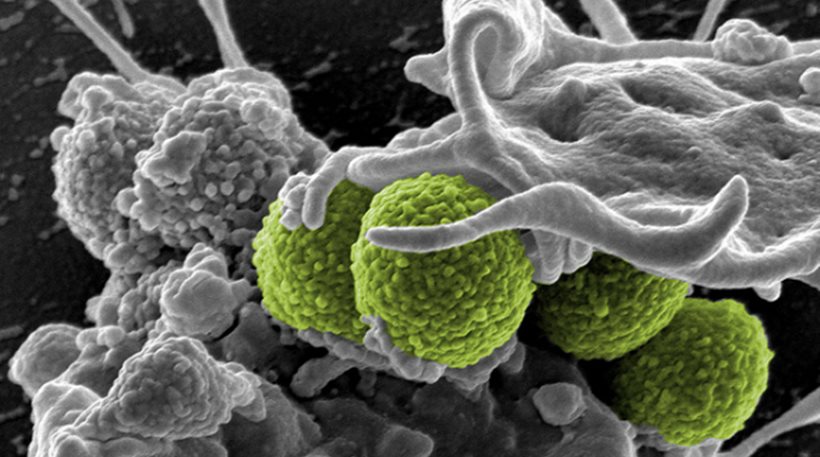

Η ανθεκτικότητα των υπερμικροβίων είναι μια ανησυχητική απειλή που θέτει σε κίνδυνο την υγεία των ανθρώπων και των ζώων”, ανακοίνωσε...